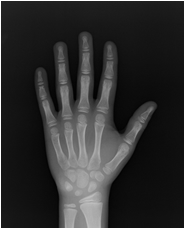

骨年齢を割り出す方法はいくつかありますが、基本的に左手のレントゲン写真(図)を使い、手を構成するいくつかの骨の形状から骨年齢を割り出します。

• 暦年齢12.7歳 骨年齢:13.3歳

図)アカデミー試験での骨年齢評価のための左手レントゲン写真。すべて小学6年生で、暦年齢はほぼ同じですが、レントゲン写真でも明らかなように手を構成する骨の成熟に違いがあるのがわかります。骨年齢は10~13.3歳と幅がみられています。